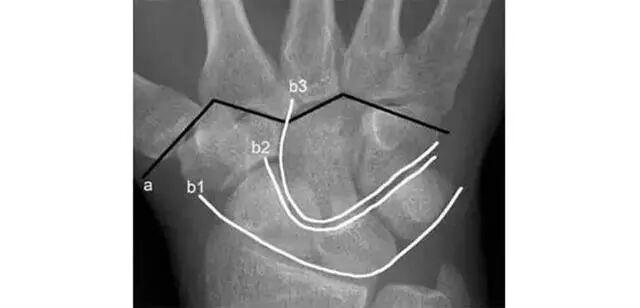

两条弧线 如果不连通 多半有脱位

若显示腕骨弧线不连续或各弧线不平行,或腕掌线M形结构消失,应高度怀疑腕关节不稳或脱位。

Analyze-腕骨弧线正位弧线不连续,侧位明显脱位。